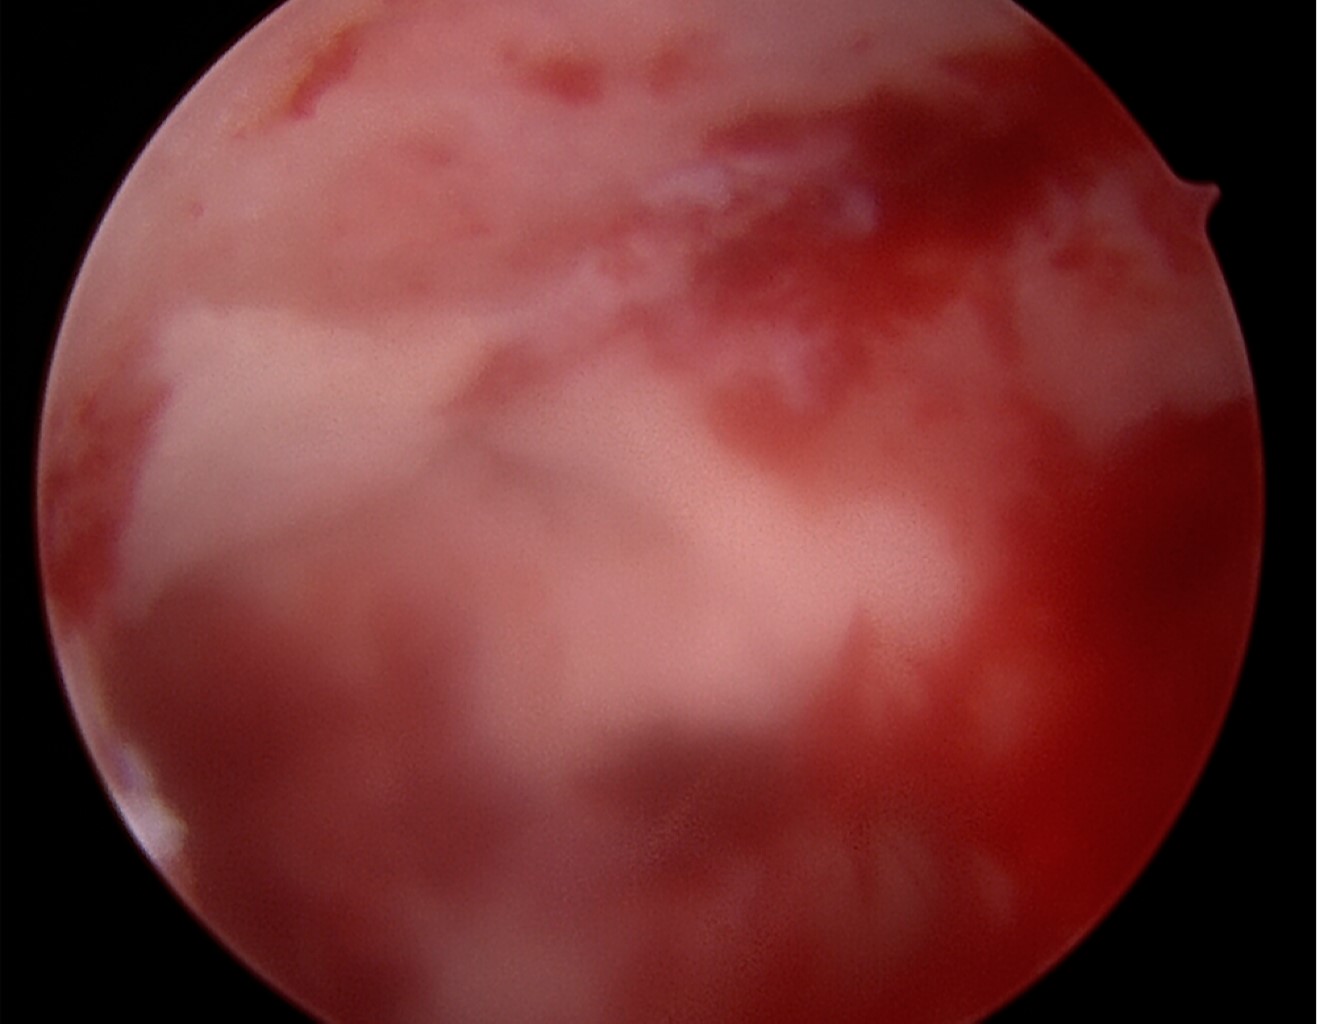

A la examinación artroscópica observamos cuerpos libres intraarticulares y daño condral en superficie en contacto con material de osteosíntesis (Figura 4). A través de túnel transóseo documentamos protrusión de material de osteosíntesis y contacto con superficie articular coxofemoral. La examinación dinámica mediante movilización de cadera derecha nos permitió observar zonas de lesión condral grado 4 de Outerbridge en la superficie de contacto de hélice en acetábulo posteromedial (Figura 5). Las superficies desprovistas de cartílago desbridaron con rasurador eléctrico hasta obtener bordes estables. Posterior al desbridamiento se documentó una zona lesional de menos de 1 cm2, por lo que nuestro tratamiento fue la regularización de los bordes y la estabilización del cartílago restante.

Figura 4

Figura 5